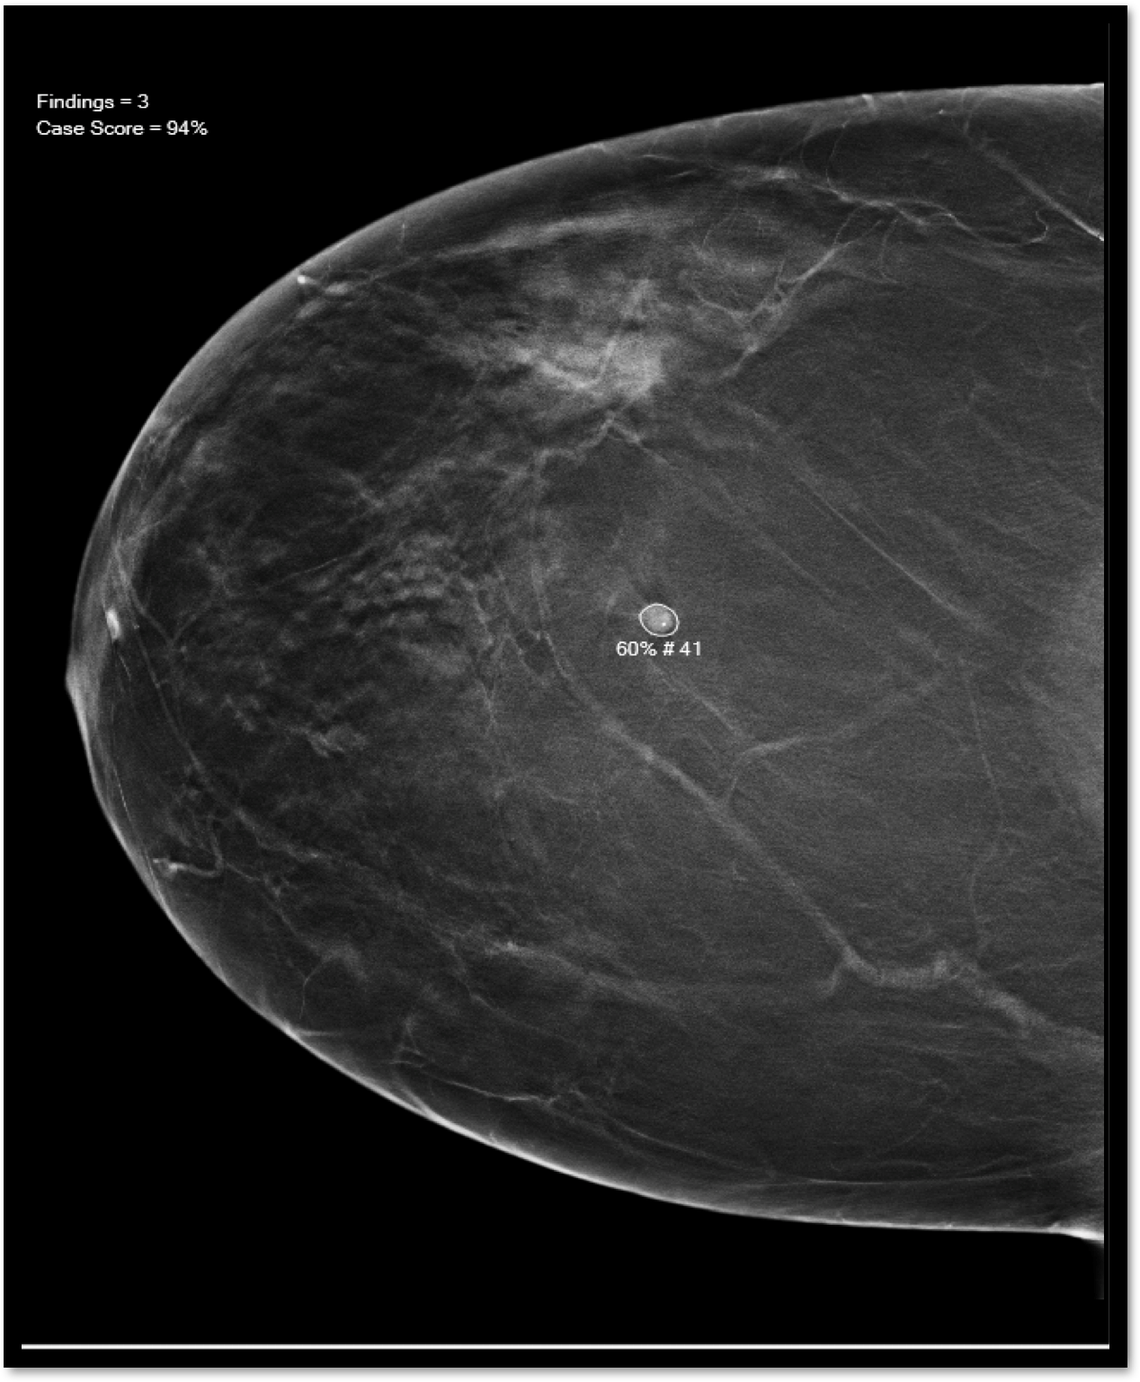

The 3D mammography creates four images using hundreds of stills that are converted into thin 1-millimeter images per exam. The AI system acts like a second pair of eyes.

It scans the images and notifies radiologists of possible cancer spots, circling the area and giving it a number on a scale for the likelihood of cancer. The radiologist still needs to examine the image, and consider the patient’s age and risk factors, to determine whether further evaluation is needed.